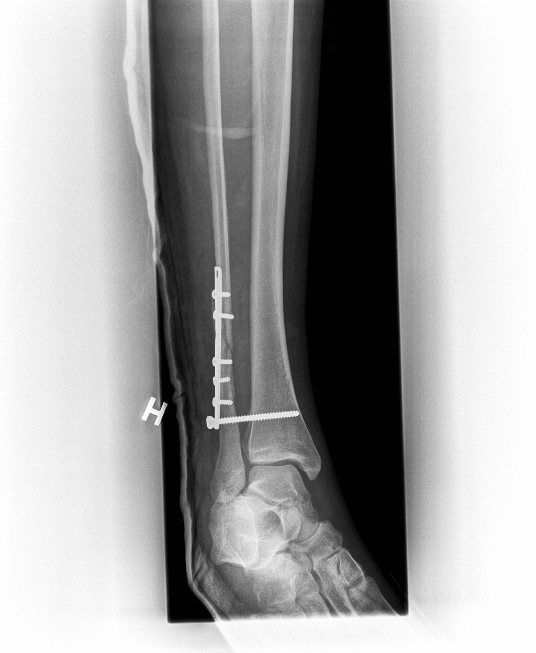

- Anja breaks her leg .... emptying the garbage: her second field trip to Svalbard in April has to be potponed

Anja's x-rays showing the break (left) and the repair job (right).